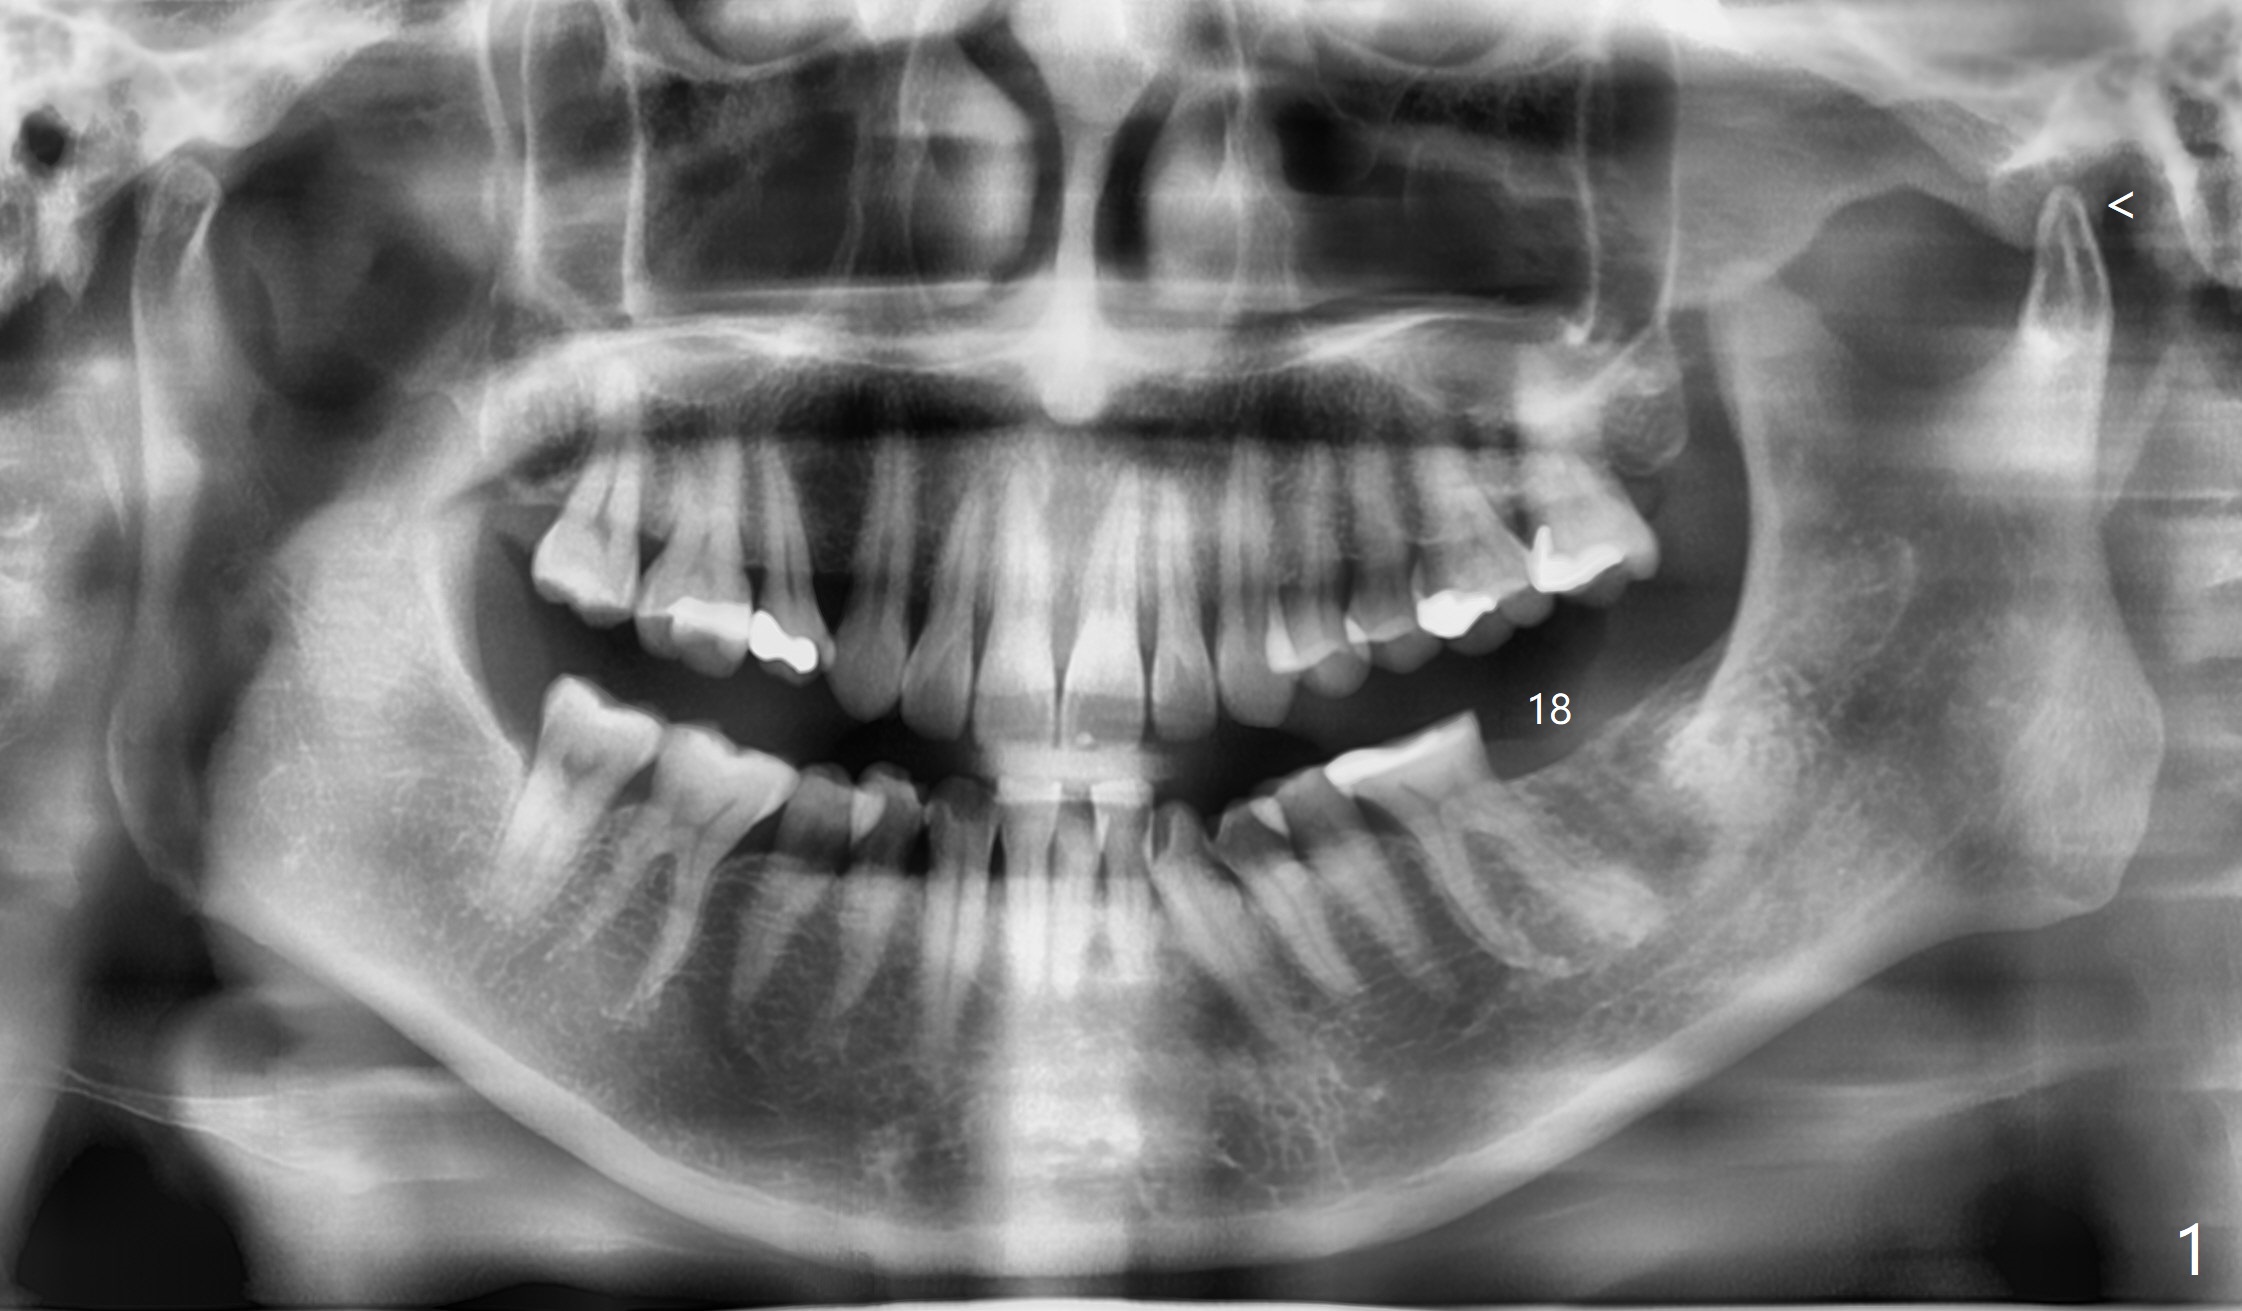

A 57-year-old woman has left TMD (Fig.1 <) and food impaction between #3 and 4 eight months post #18 extraction apparently without bone graft in China. There is anterior deep bite with severe lower anterior crowding. She had unsuccessful ortho in her young age in China. She is interested in ortho. Ortho referral is recommended. Occlusal wear is severe, especially at #19 and 30. It appears that comprehensive treatment is required. In fact impression has been taken for #18 guide (Fig.2). A challenge is limited mouth opening. Splint should be tried for TMD. The hard and uneven ridge (Fig.2 arrowhead) will be securely trimmed with flap surgery and surgical handpiece rather than bone trimmer.